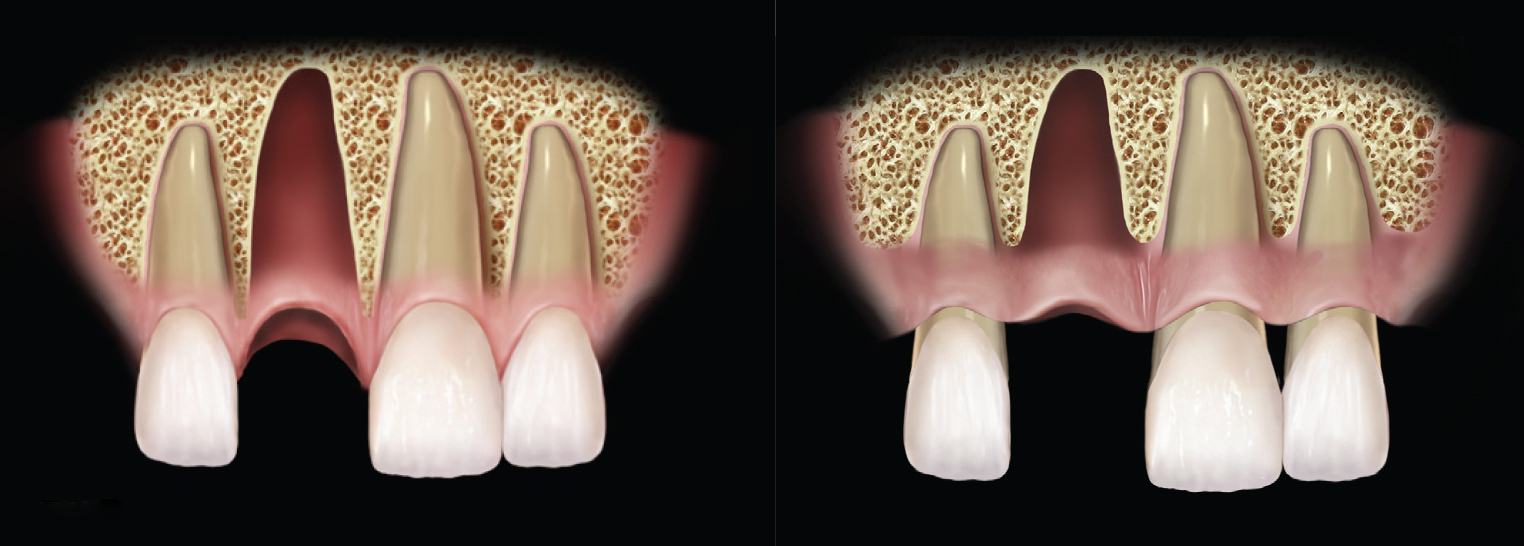

(Left) Example of adequate interproximal bone. The periodontium is healthy, and the bony peeks on either side of the extraction socket are aiding in supporting the interproximal papilla. (Right) A mildly reduced periodontium. Interproximal bone is present; there is enough bone to support full papilla in the embrasure spaces of the natural dentition.

Interproximal bone levels influence the healing of the socket and the support of the interproximal soft tissue following implant placement. The presence or absence of papilla between an implant and a natural tooth is dependent on the level of interproximal bone. Therefore, the height of the interproximal bone plays a significant role in the final esthetic outcome when replacing a failing tooth with an implant-supported restoration.4,5

The interproximal bone affects the healing of an extraction socket, because this bone along with the buccal and lingual bone makes up the walls of a socket. After tooth extraction, a blood clot will form within the confines of the extraction socket walls; this blood clot will serve as the scaffold for bone formation, turning into woven and, then eventually, mature trabecular bone.6 As the interproximal, lingual, and buccal bone all support the initial blood clot, their height affects the dimension of the blood clot and, therefore, impacts the final bone morphology.